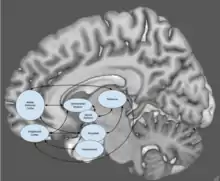

Neural circuits implicated in depression include those involved in the generation and regulation of emotion, as well as in reward. Abnormalities are commonly found in the lateral prefrontal cortex whose putative function is generally considered to involve regulation of emotion. Regions involved in the generation of emotion and reward such as the amygdala, anterior cingulate cortex (ACC), orbitofrontal cortex (OFC), and striatum are frequently implicated as well. These regions are innervated by a monoaminergic nuclei, and tentative evidence suggests a potential role for abnormal monoaminergic activity.[6][7]

Neural circuits

One meta analysis of functional neuroimaging in depression observed a pattern of abnormal neural activity hypothesized to reflect an emotional processing bias. Relative to controls, people with MDD showed hyperactivity of circuits in the salience network (SN), composed of the pulvinar nuclei, the insula, and the dorsal anterior cingulate cortex (dACC), as well as decreased activity in regulatory circuits composed of the striatum and dlPFC.[72]

A neuroanatomical model called the limbic-cortical model has been proposed to explain early biological findings in depression. The model attempts to relate specific symptoms of depression to neurological abnormalities. Elevated resting amygdala activity was proposed to underlie rumination, as stimulation of the amygdala has been reported to be associated with the intrusive recall of negative memories. The ACC was divided into pregenual (pgACC) and subgenual regions (sgACC), with the former being electrophysiologically associated with fear, and the latter being metabolically implicated in sadness in healthy subjects. Hyperactivity of the lateral orbitofrontal and insular regions, along with abnormalities in lateral prefrontal regions was suggested to underlie maladaptive emotional responses, given the regions roles in reward learning.[74][75] This model and another termed "the cortical striatal model", which focused more on abnormalities in the cortico-basal ganglia-thalamo-cortical loop, have been supported by recent literature. Reduced striatal activity, elevated OFC activity, and elevated sgACC activity were all findings consistent with the proposed models. However, amygdala activity was reported to be decreased, contrary to the limbic-cortical model. Furthermore, only lateral prefrontal regions were modulated by treatment, indicating that prefrontal areas are state markers (i.e., dependent upon mood), while subcortical abnormalities are trait markers (i.e., reflect a susceptibility).[76]

Brain regions

Research on the brains of people with MDD usually shows disturbed patterns of interaction between multiple parts of the brain. Several areas of the brain are implicated in studies seeking to more fully understand the biology of depression:

Subgenual cingulate

Studies have shown that Brodmann area 25, also known as subgenual cingulate, is metabolically overactive in treatment-resistant depression. This region is extremely rich in serotonin transporters and is considered as a governor for a vast network involving areas like hypothalamus and brain stem, which influences changes in appetite and sleep; the amygdala and insula, which affect the mood and anxiety; the hippocampus, which plays an important role in memory formation; and some parts of the frontal cortex responsible for self-esteem. Thus disturbances in this area or a smaller than normal size of this area contributes to depression. Deep brain stimulation has been targeted to this region in order to reduce its activity in people with treatment resistant depression.[107]: 576–578 [108]

Prefrontal cortex

One review reported hypoactivity in the prefrontal cortex of those with depression compared to controls.[109] The prefrontal cortex is involved in emotional processing and regulation, and dysfunction of this process may be involved in the etiology of depression. One study on antidepressant treatment found an increase in PFC activity in response to administration of antidepressants.[110] One meta analysis published in 2012 found that areas of the prefrontal cortex were hypoactive in response to negative stimuli in people with MDD.[72] One study suggested that areas of the prefrontal cortex are part of a network of regions including dorsal and pregenual cingulate, bilateral middle frontal gyrus, insula and superior temporal gyrus that appear to be hypoactive in people with MDD. However the authors cautioned that the exclusion criteria, lack of consistency and small samples limit results.[106]

Amygdala

The amygdala, a structure involved in emotional processing appears to be hyperactive in those with major depressive disorder.[108] The amygdala in unmedicated depressed persons tended to be smaller than in those that were medicated, however aggregate data shows no difference between depressed and healthy persons.[111] During emotional processing tasks right amygdala is more active than the left, however there is no differences during cognitive tasks, and at rest only the left amygdala appears to be more hyperactive.[112] One study, however, found no difference in amygdala activity during emotional processing tasks.[113]

Hippocampus